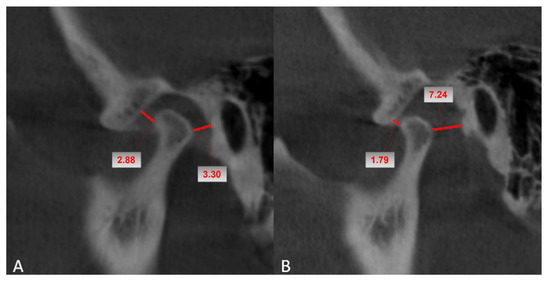

2. Materials and Methods